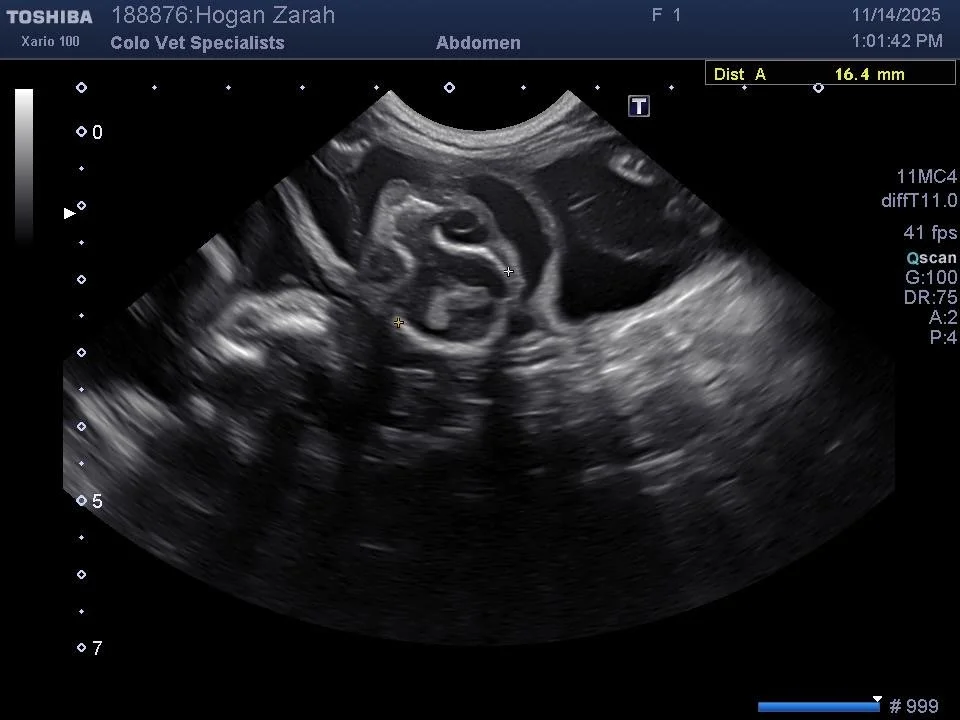

Maine Coon kitten ultrasound showing the head of a kitten.